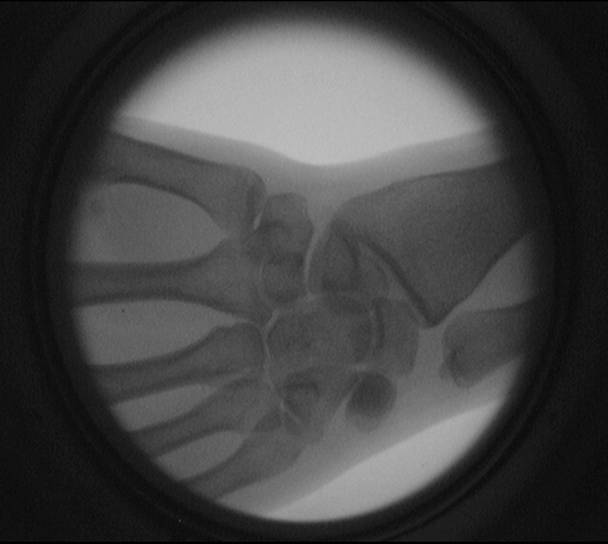

電熱絲和電熱絲的接口 手關節透視圖

電熱絲內部結構 品字插孔和三芯電源插頭